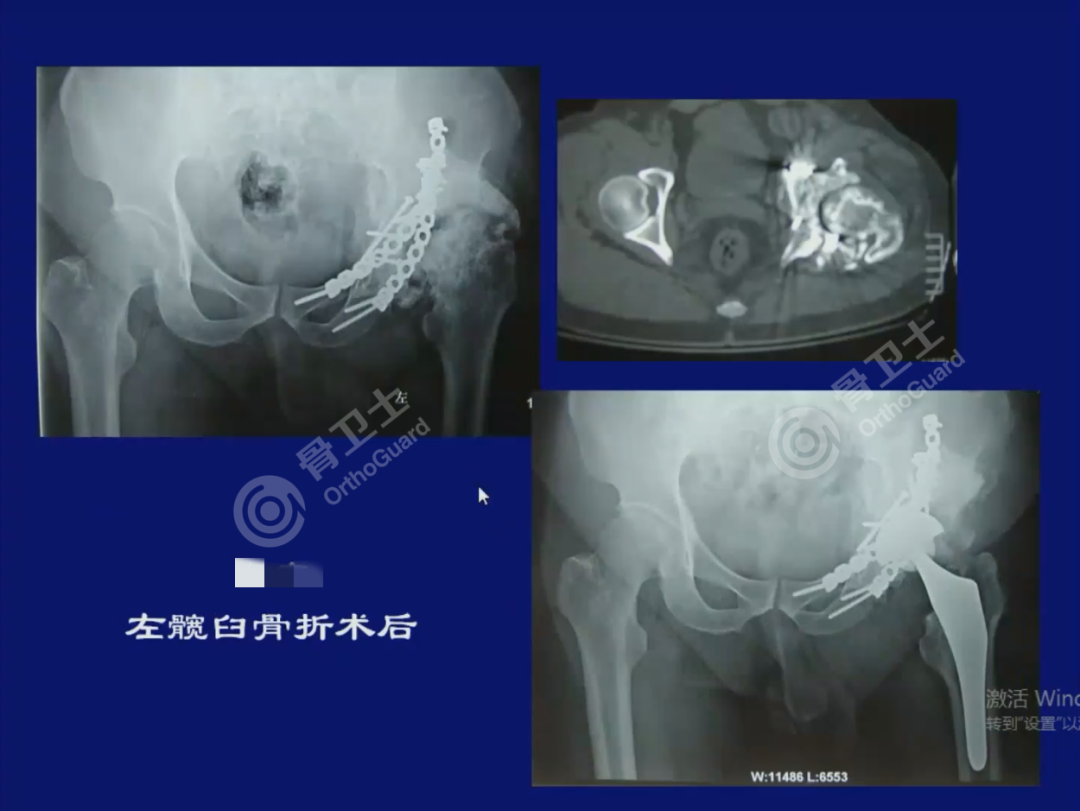

▲陈旧性髋臼骨折病例资料